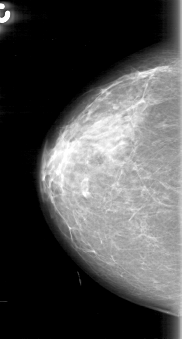

D_4057_1.LEFT_MLO

LEFT_MLO LINES 5281 PIXELS_PER_LINE 3061 BITS_PER_PIXEL 12 RESOLUTION 43.5 OVERLAY